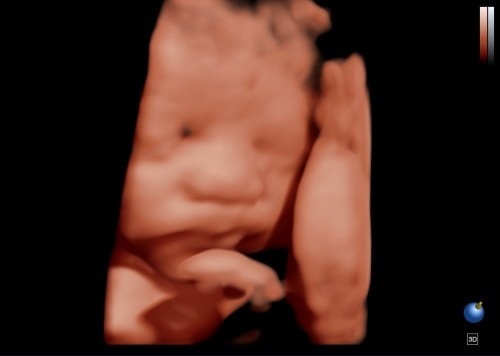

37+1 Weeks

37+1 ปวดท้องเตือน ตั้งแต่เมื่อคืน ปวดไม่มาก ปวดๆหายๆ หมอนัด 20 เมษา 64 จะคลอดก่อนไหมน่า😅🥰